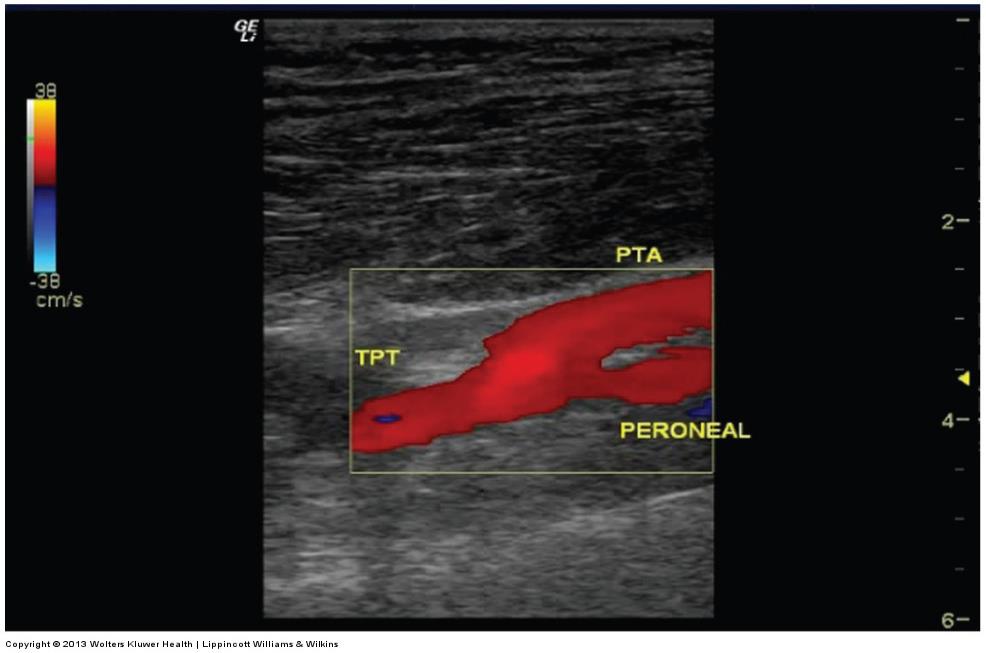

ultrasound image of the posterior tibial artery (PTA) and peroneal arteries arising off the tibioperoneal trunk